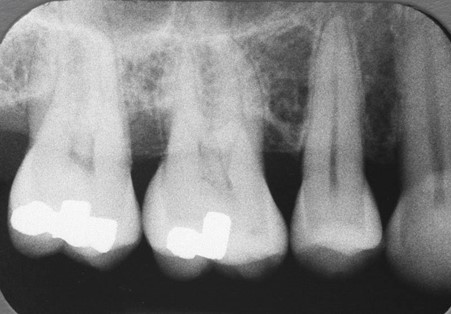

Periodontal disease comprises of a group of diseases affecting the supporting structures of the teeth (periodontium). The most common forms of periodontal disease are caused by bacteria (dental plaque) which reside on the tooth surface, and when left to mature are able to cause an infection of the gums. The end result of this infection is loss of the bone which supports the tooth, which can eventually lead to tooth mobility and tooth loss. The loss of bone support with periodontal disease is in most cases irreversible.

Susceptibility to disease and rate of progression to disease are related to bacterial pathogenicity, individual host responses to the periodontal pathogens, as well as inherent or acquired modifying factors (related to genetic susceptibility and environmental factors). Smoking is by far the biggest preventable risk factor for periodontal disease.

The initial appointment with the periodontist involves a thorough examination and assessment of the gums. This assessment is made through the measurement of the gum pockets (periodontal probing) which will reflect the gum health.

Clinical measurements of gum health will be compared with any radiographic data available, and will enable a diagnosis of your gum condition to be made. A treatment plan will be suggested and discussed with you. As periodontal disease is a chronic condition, commonly no treatment is performed during the consultation appointment.